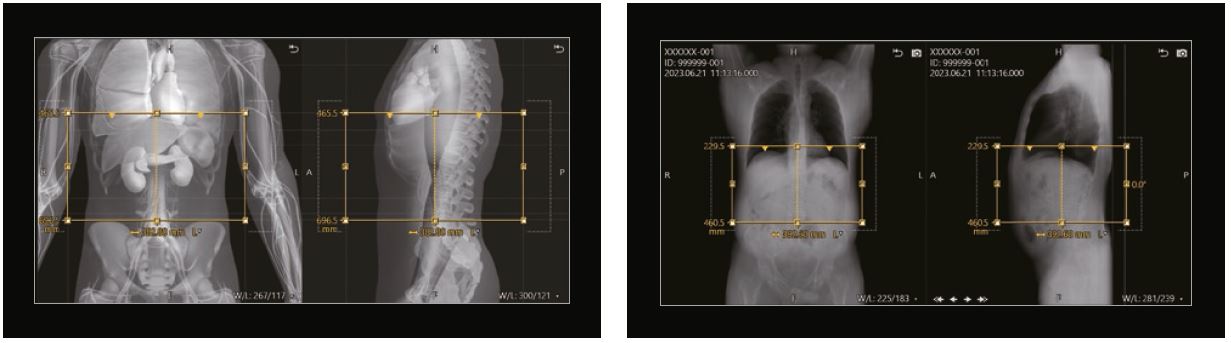

Під час створення протоколу користувач може скористатися перевагами інтерактивного анатомічного аватара, щоб вказати бажане початкове та кінцеве розташування. Наприклад, як показано на рисунку 4, цей протокол черевної порожнини починається на 1 см над куполом діафрагми та закінчується на гребені клубової кістки. На основі цих визначених користувачем «точок прив’язки» ALD використовує переваги тривимірної анатомічної інформації в зображеннях 3D Landmark Scan для автоматичного створення початкового та кінцевого положень, а також поля зору для окремого пацієнта, який сканується, з точністю 97%. Для зручності оператора ці області діапазону сканування проектуються на фронтальну та сагітальну площини, якщо з будь-якої причини потрібне ручне коригування.

Рисунок 4: Протокол черевної порожнини, що показує діапазон сканування, встановлений у протоколі сканування, а потім у фактичному дослідженні пацієнта.